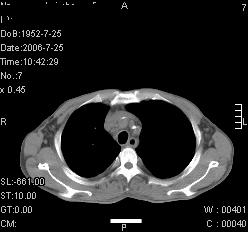

患者,男,54岁,咳嗦,咳痰20天。抗炎治疗2周。现esr76mm/h,目前患者症状明显好转,但发现两次ct片未见明显变化。两次分别做与7.25、7.31。第一次诊断右肺上叶炎症累计胸膜。大家看,从影像上内排除结核吗?

结核的可能性非常大,右上肺病变应该考虑干酪性肺炎。理由:

1.纵隔内多发淋巴结肿大。

3.虽经抗炎治疗肺窗病灶有所吸收、减小,但纵隔窗病灶形态、密度、范围无明显变化。如果是单纯的大叶性肺炎,“抗炎治疗2周,目前患者症状明显好转”病灶应该基本消散了,至少也处于吸收消散期,密度变淡、范围变小。同时本病例所示其内的密度不均匀,见多发大小不一空洞样影也不符合大叶性肺炎吸收消散期表现。

病灶特点:片状 索条 结节混杂影,部分融合,密度不均,广泛累及相应胸膜.

临床治疗;二周未吸收.但症状好转.

多考虑:肺结核.